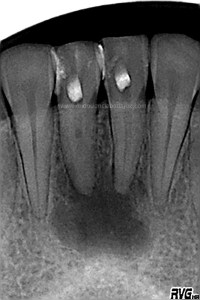

Se le volvió a llamar para otra revisión al año y medio para ver como iba evolucionando:

(revisión al año y 6 meses)